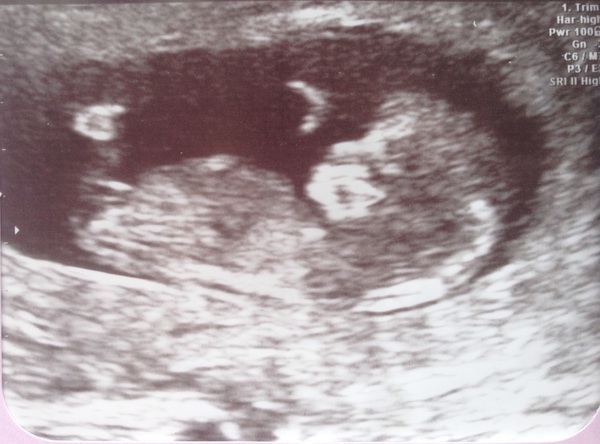

I haven't posted in ages but had my 12 week scan today and official due date is March 26th which I believe is Mother's Day! Here's my scan - so beyond happy!